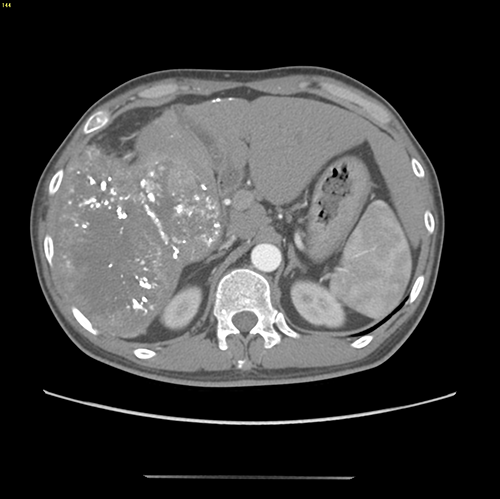

右肝巨大肝癌---右半肝切除